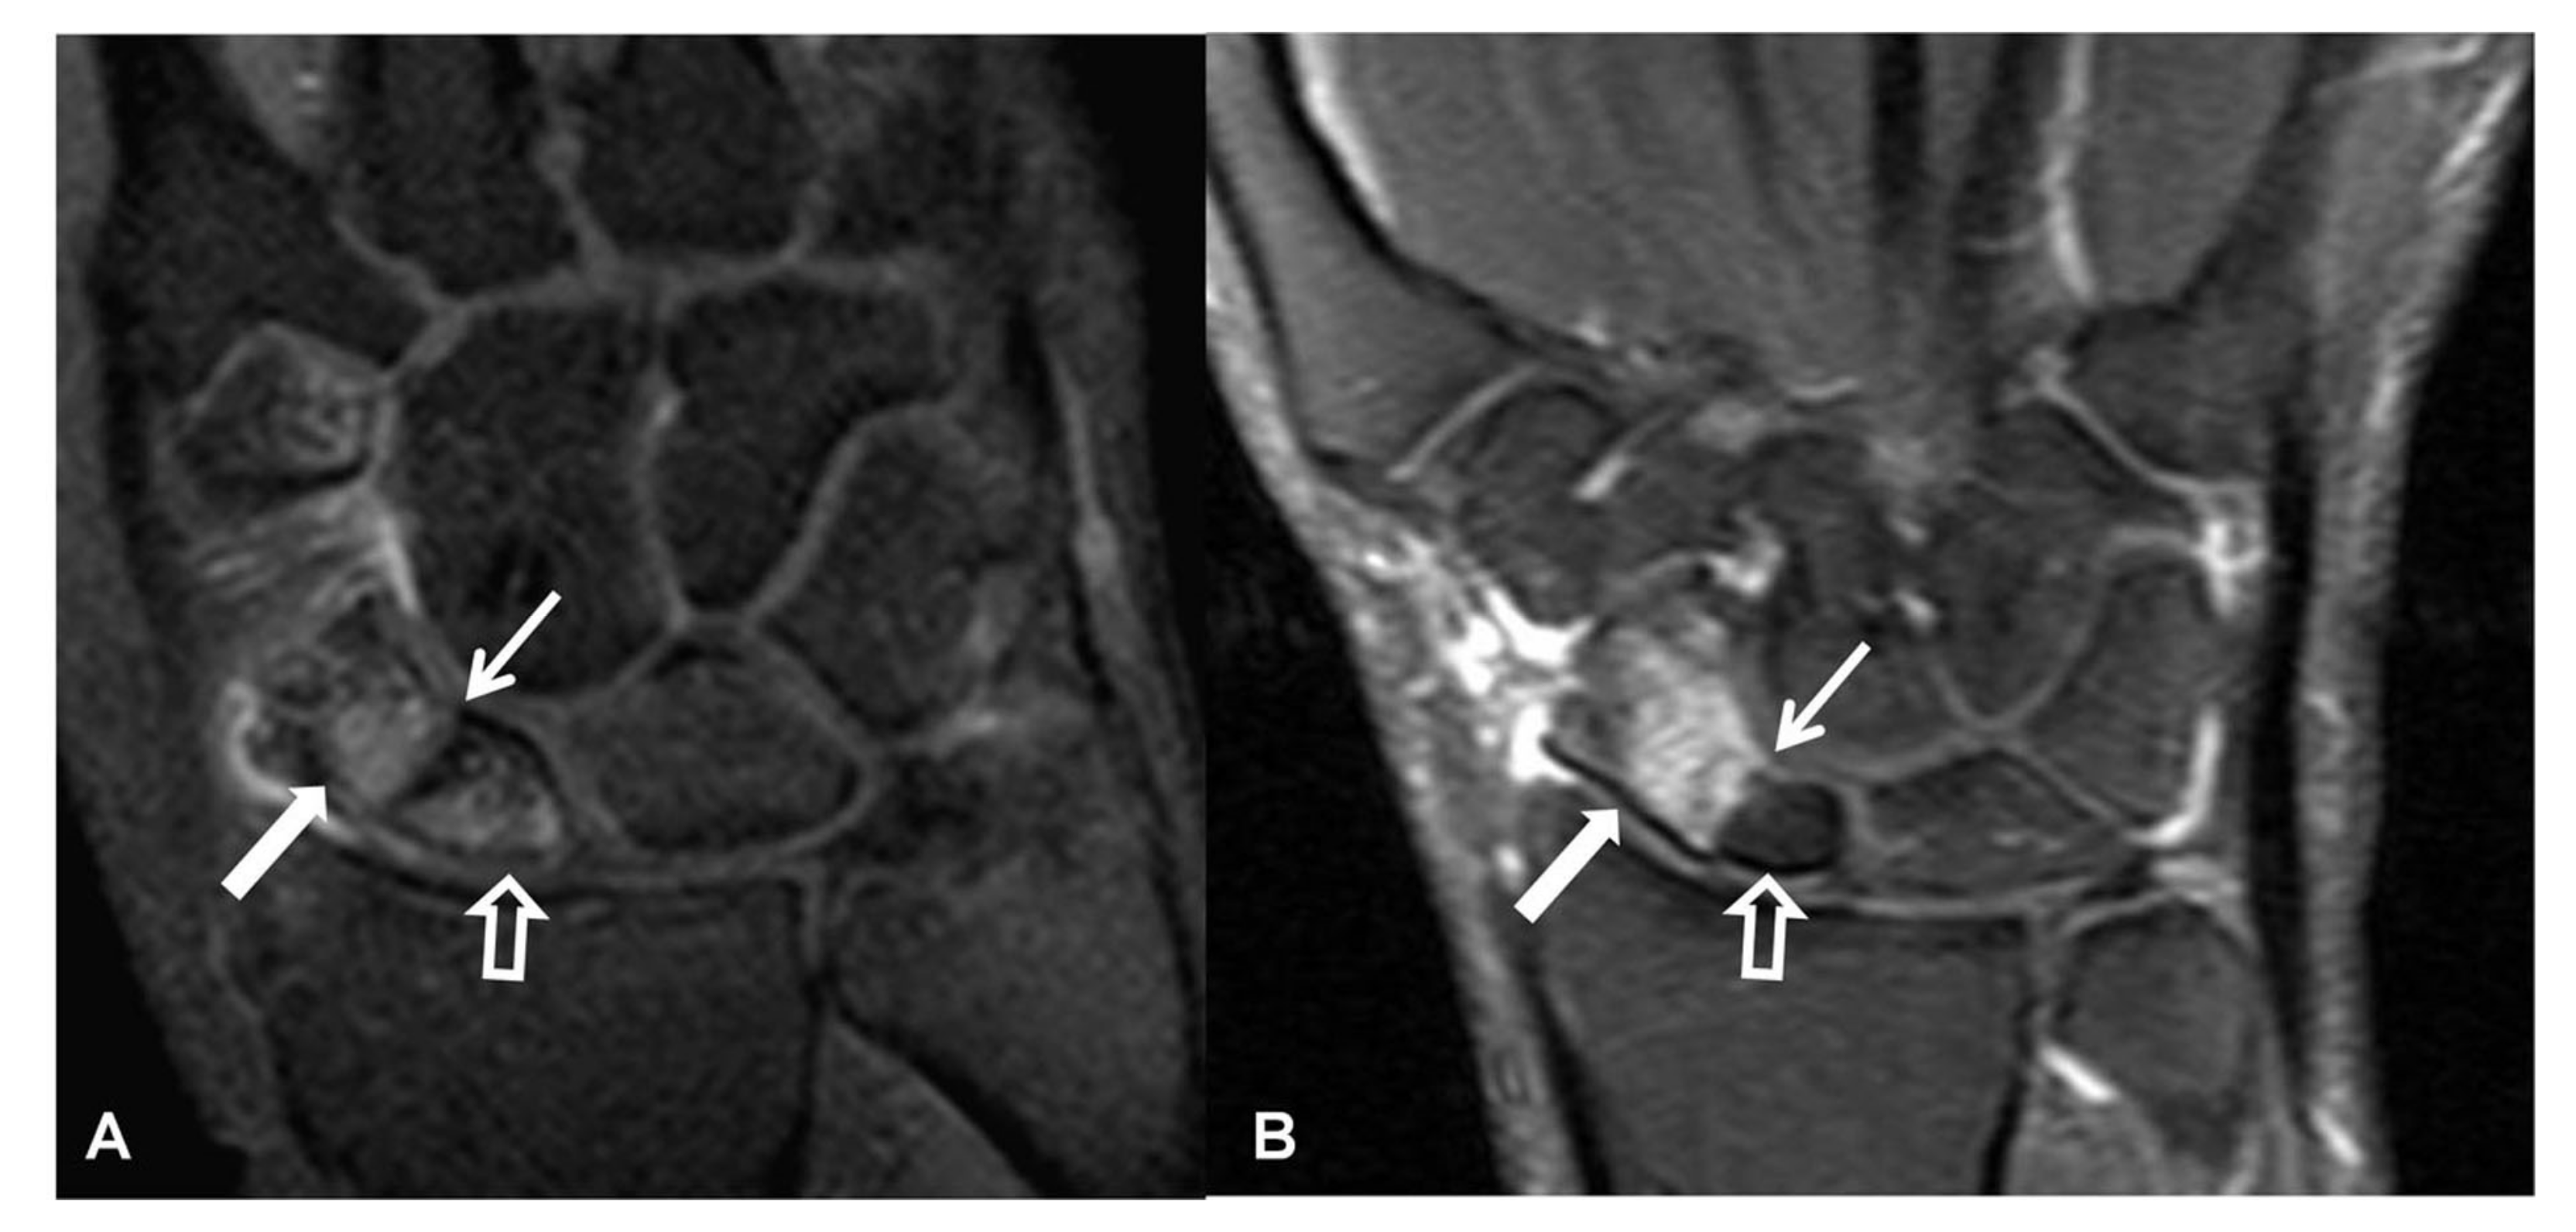

Figure 11.

Two patients with scaphoid fracture non-union, fat suppressed contrast enhanced T1w coronal MR images. Both images show the fracture line (thin arrows) and the normal enhancement following a fracture, of the distal pole of the scaphoid bones (thick arrows). (A) Enhancement of the proximal pole suggests viable bone marrow (open arrow). (B) Absence of any enhancement of the proximal pole suggests nonviable bone marrow (open arrow). The signal intensity of the proximal pole is lower as compared to the normal bone marrow of the surrounding bones.